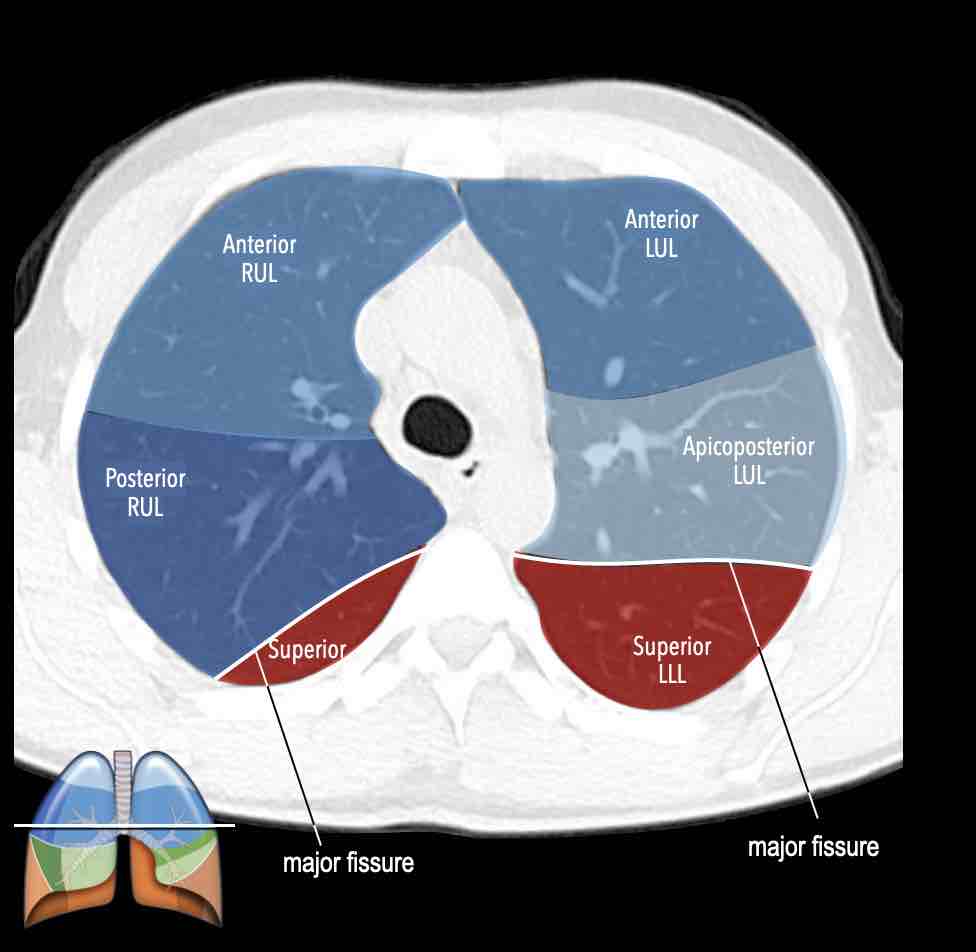

Các phân thùy phổi trên CT

Cuộn qua các hình ảnh để quan sát cách phổi được phân chia thành các phân thùy.